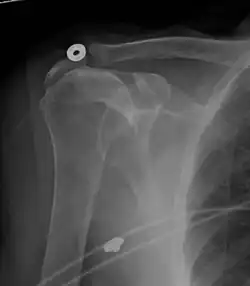

A complete tear of the supraspinatus resulting in a shift upwards of the head of the humerus

Projectional radiograph of normal glenohumeral position.[51]

High-riding humeral head in a rotator cuff tear.

X-ray projectional radiography cannot directly reveal tears of the rotator cuff, a 'soft tissue', and consequently, normal X-rays cannot exclude a damaged cuff. However, indirect evidence of pathology may be seen in instances where one or more of the tendons has undergone degenerative calcification (calcific tendinitis). The humeral head may migrate upward (high-riding humeral head) secondary to tears of the infraspinatus, or combined tears of the supraspinatus and infraspinatus.[51] The migration can be measured by the distance between:

• A line crossing the center of a line between the superior and inferior rims of the glenoid articular surface (blue in image).

• The center of a "best-fit" circle positioned over the humeral articular surface (green in image)

Normally, the former is positioned inferiorly to the latter, and a reversal therefore indicates a rotator cuff tear.[51] Prolonged contact between a high-riding humeral head and the acromion above it may lead to X-ray findings of wear on the humeral head and acromion; secondary degenerative arthritis of the glenohumeral joint (the ball and socket joint of the shoulder), called cuff arthropathy, may follow.[50] Incidental X-ray findings of bone spurs at the adjacent acromioclavicular joint may show a bone spur growing from the outer edge of the clavicle downward toward the rotator cuff. Spurs may also be seen on the underside of the acromion, once thought to cause direct fraying of the rotator cuff from contact friction, a concept currently regarded as controversial.